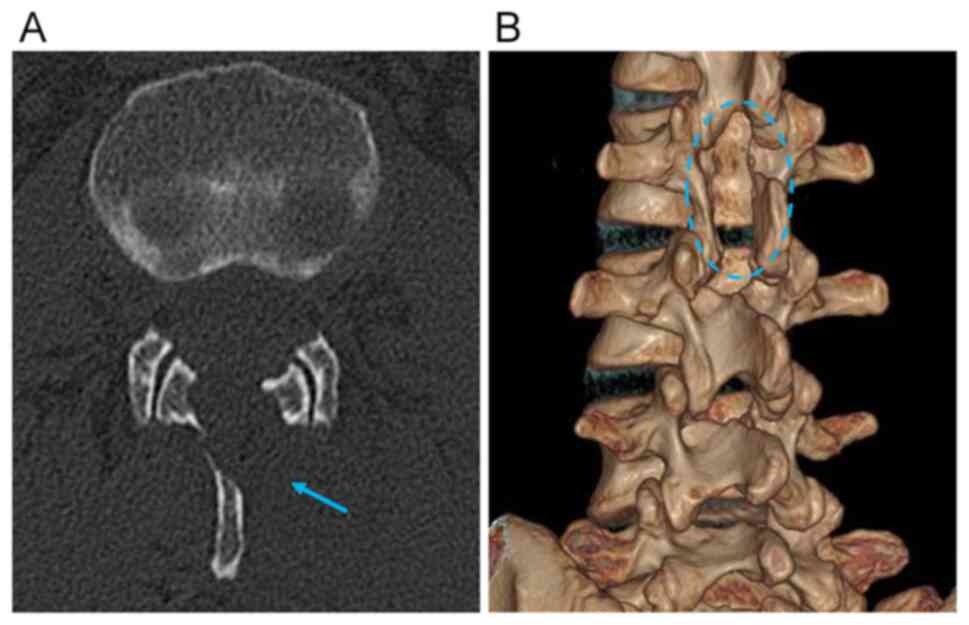

Pure endoscopic minimally invasive surgery with a non‑expandable tubular retractor for intradural extramedullary spinal tumors

Minimally invasive spinal surgery (MISS) for intradural extramedullary (IDEM) spinal tumors is a safe and effective surgical strategy. Currently, various tubular retractors are widely used in the MISS of IDEM spinal tumors, primarily relying on microscopic visualization. To the best of the authors' knowledge, there is no report of pure endoscopic surgery with parallel non‑expandable tubular retractors for IDEM spinal lesions. The present study reports a case series of IDEM spinal tumors that were treated via pure endoscopic MISS with a parallel non‑expandable tubular retractor. The extent of tumor resection was evaluated by comparing preoperative and postoperative magnetic resonance imaging (MRI). The initial and follow‑up clinical conditions were assessed according to the visual analog scale for pain and the modified McCormick scale for neurological status. Postoperative MRI demonstrated that all cases had achieved a gross total resection. After the operation, the clinical symptoms of all patients were significantly improved and there were no serious postoperative complications. At the initial follow‑up, the pain experienced by the patients was significantly reduced or had even disappeared, and the neurological deficit was improved by at least one grade on the modified McCormick scale. The present report indicates that pure endoscopic MISS with a parallel non‑expandable tubular retractor may be an effective and safe surgical strategy for IDEM spinal tumor resection.

Figure 1